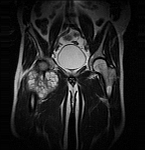

• Extensive reconstructive procedures for the reconstruction of large pelvic bone defects